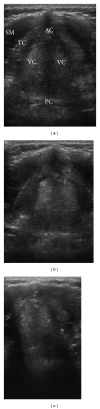

Ultrasound is a safe, portable, relatively inexpensive, and easily accessible imaging modality, making it a useful diagnostic and monitoring tool in medicine. Anesthesiologists encounter a variety of emergent situations and may benefit from the application of such a rapid and accurate diagnostic tool in their routine practice. This paper reviews current and potential applications of ultrasound in anesthesiology in order to encourage anesthesiologists to learn and use this useful tool as an adjunct to physical examination. Ultrasound-guided peripheral nerve blockade and vascular access represent the most popular ultrasound applications in anesthesiology. Ultrasound has recently started to substitute for CT scans and fluoroscopy in many pain treatment procedures. Although the application of airway ultrasound is still limited, it has a promising future. Lung ultrasound is a well-established field in point-of-care medicine, and it could have a great impact if utilized in our ORs, as it may help in rapid and accurate diagnosis in many emergent situations. Optic nerve sheath diameter (ONSD) measurement and transcranial color coded duplex (TCCD) are relatively new neuroimaging modalities, which assess intracranial pressure and cerebral blood flow. Gastric ultrasound can be used for assessment of gastric content and diagnosis of full stomach. Focused transthoracic (TTE) and transesophageal (TEE) echocardiography facilitate the assessment of left and right ventricular function, cardiac valve abnormalities, and volume status as well as guiding cardiac resuscitation. Thus, there are multiple potential areas where ultrasound can play a significant role in guiding otherwise blind and invasive interventions, diagnosing critical conditions, and assessing for possible anatomic variations that may lead to plan modification. We suggest that ultrasound training should be part of any anesthesiology training program curriculum.